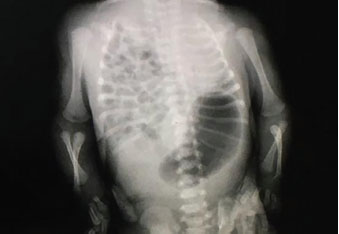

Se tomó una radiografía de tórax donde se observa presencia de asas intestinales en la cavidad torácica derecha y en la base pulmonar izquierda, y desplazamiento del mediastino y del corazón hacia la izquierda (Figura 1), hipoplasia pulmonar severa por compresión en el hemitórax derecho. Con hallazgos al examen físico de murmullo vesicular inaudible en ambos campos pulmonares, con peristalsis presente en todo el campo pulmonar derecho y en la base del pulmón izquierdo, con retracción costal, abdomen excavado, depresible, con ausencia de peristalsis y vísceras no palpables, además con cianosis generalizada. Se interconsultó con Cirugía Pediátrica y se decide el traslado del paciente a otro centro de salud más especializado, donde se realizó un ecocardiograma que evidenció hipertensión pulmonar moderada, secundaria a su patología de base.

Figura 1. Radiografía. Reducción del parénquima pulmonar en el hemitórax izquierdo y desplazamiento del mediastino y del corazón hacia la izquierda, además de presencia de asas intestinales en la cavidad torácica derecha